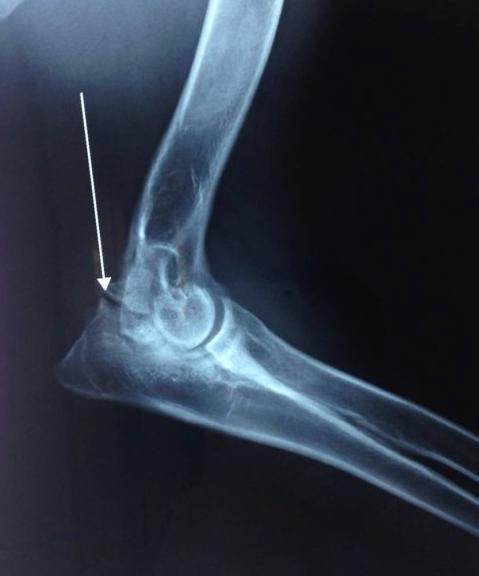

关节软骨无法在特定位置转变为骨骼,直接令到这区域的软骨增厚,增厚的软骨与周围正常的软骨分离形成了皮瓣,这一系列过程便称之为OCD。异常软骨的皮瓣有可能会发生从关节表面脱离,形成“关节鼠”。

图为“关节鼠”

那么,什么是“关节鼠”?

这一术语较好理解,意指关节出现病变的时候,在关节软骨内部会有自行脱离的“小碎片”。如前文提到,关节之间有“小碎片”的存在,容易发生疼痛等一系列影响。